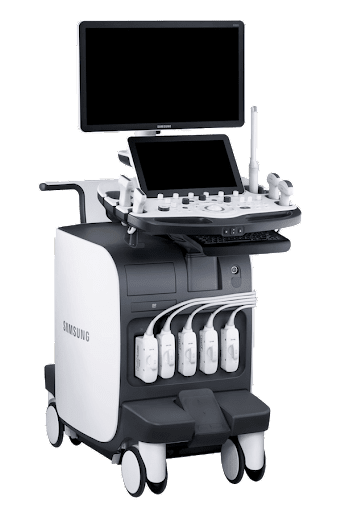

УЗИ-аппарат Samsung RS85 Prestige

Ультразвуковой аппарат экспертного класса подходит для решения большого спектра клинических задач. Сочетает в себе высокую производительность, идеальное качество изображения и незаменимый функционал.

RS85 Prestige — УЗИ-аппарат экспертного класса. Сочетает в себе качественную визуализацию, набор экспертных программ, возможности искусственного интеллекта и оптимизированный интерфейс. Позволяет врачу быстро обнаружить очаг патологии, определить природу его возникновения и соответственно – уверенно поставить диагноз.

Оборудование эргономично впишется в повседневную практику любой клиники. Технические характеристики разработаны таким образом, чтобы процесс исследования был максимально комфортен для врача и пациента. Аппарат рекомендован для медицинских исследовательских институтов и лечебных учреждений с высокими требованиями к ультразвуковой диагностике.

- Монитор: 23,8″ Full HD

- Сенсорная панель управления (touch-screen): 13.3″

- Разъемы: для одновременного подключения до 5-х датчиков (4 + 1 CW), есть также 1 парковочное место для 6 датчика

- USB-порты (для подключения периферических устройств, внешних накопителей: флеш-карт или DVD)

- Напряжение: 100-240 Вт

- Типы соединения: DICOM , USB

- Жесткий диск: 512 Гб

- Датчики: Конвексный , Линейный , Секторный , Фазированный , Внутриполостные , Чреспищеводный

- Режимы сканирования: B-Режим , M-Режим , 3D , 4D , Непрерывно-волновой допплеровский режим CW